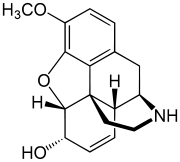

Several semi-synthetic opioids were developed in Germany in the 1910s. The first, oxymorphone, was synthesized from thebaine, an opioid alkaloid in opium poppies, in 1914.[228] Next, Martin Freund and Edmund Speyer developed oxycodone, also from thebaine, at the University of Frankfurt in 1916.[229] In 1920, hydrocodone was prepared by Carl Mannich and Helene Löwenheim, deriving it from codeine. In 1924, hydromorphone was synthesized by adding hydrogen to morphine. Etorphine was synthesized in 1960, from the oripavine in opium poppy straw. Buprenorphine was discovered in 1972.[228]